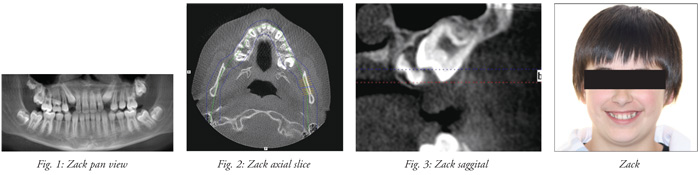

Meet Zack, a typical teenager visiting my orthodontic office. His maxillary second molar, tooth #15, was not erupting as seen radiographically over time. Previous 2D progress panoramic X-rays were unremarkable other than showing #15 not making eruptive progress (Fig. 1). Our recent 3D scan captured by my i-CAT, showed that some action was going on, literally behind the scenes. After cross-sectioning the scan axially and sagitally (Figs. 2 & 3), the parents, patient and I saw that a third molar, undetectable on a 2D pan, was interfering with eruption. This finding by a 3D scan did not surprise me. Since I implemented CBCT imaging, I have found six other teens with similar circumstances in the last year and a half. While some people say, “seeing is believing,” that is not always the case with 2D imaging. In fact, without a 3D scan, my treatment plan would have been completely different.

Most likely, I would have waited six to 12 months to evaluate eruption of this tooth. If or when no progress was seen, I would have conjectured that the tooth might be ankylosed. I might have sent Zack to the oral surgeon to luxate the tooth. Depending on the surgeon’s approach to luxate or mobilize this tooth, he still might have missed the palatal third molar that was interfering with eruption. Following mobilization, we would have again waited six to 12 months and checked progress with a 2D radiograph. If progress continued to be lacking or not occurring, we would then have entertained surgical exposure and bonding with a button and chain or extraction. In Zack’s case, I could very well have followed the wrong treatment approach because of the lack of correct information.